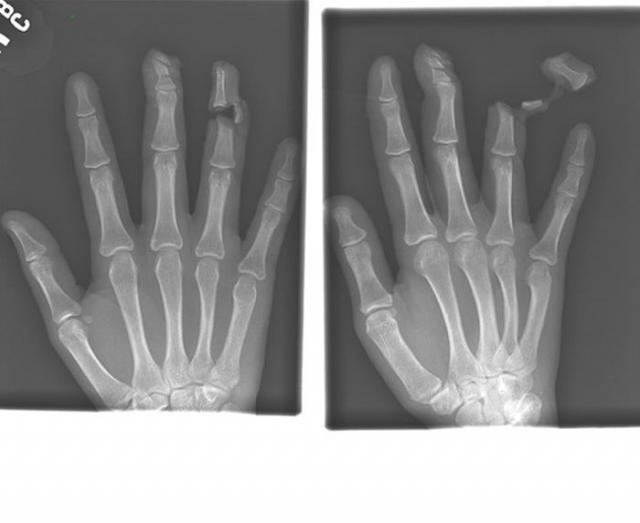

Рентгеновские снимки людей, которые умудрились сами или с чужой помощью разместить внутри своего организма разные посторонние предметы. От вилок и ножей до пуль и бензопилы (!!!). По этическим соображениям обычные снимки таких травм и повреждений выкладывать нельзя, зато рентгеновские можно – на них травмы видны достаточно условно, хоть и очень понятно.